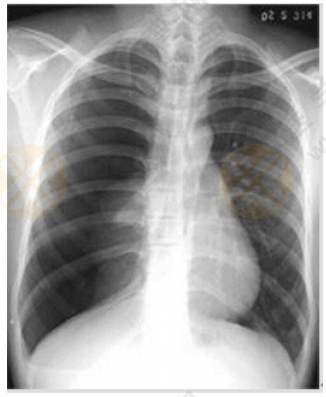

中医助理医师实践技能【西医临床答辩】02号题:根据下图所给X线片分析临床意义